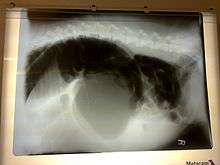

A diagnosis of gastric dilatation-volvulus is made by several factors. The breed and history will often give a significant suspicion of gastric dilatation-volvulus, and the physical exam will often reveal the telltale sign of a distended abdomen with abdominal tympany. Shock is diagnosed by the presence of pale mucous membranes with poor capillary refill, increased heart rate, and poor pulse quality. X-rays (usually taken after decompression of the stomach if the dog is unstable) will show a stomach distended with gas. The pylorus, which normally is ventral and to the right of the body of the stomach, will be cranial to the body of the stomach and left of the midline, often separated on the x-ray by soft tissue and giving the appearance of a separate gas filled pocket (double bubble sign).[17]